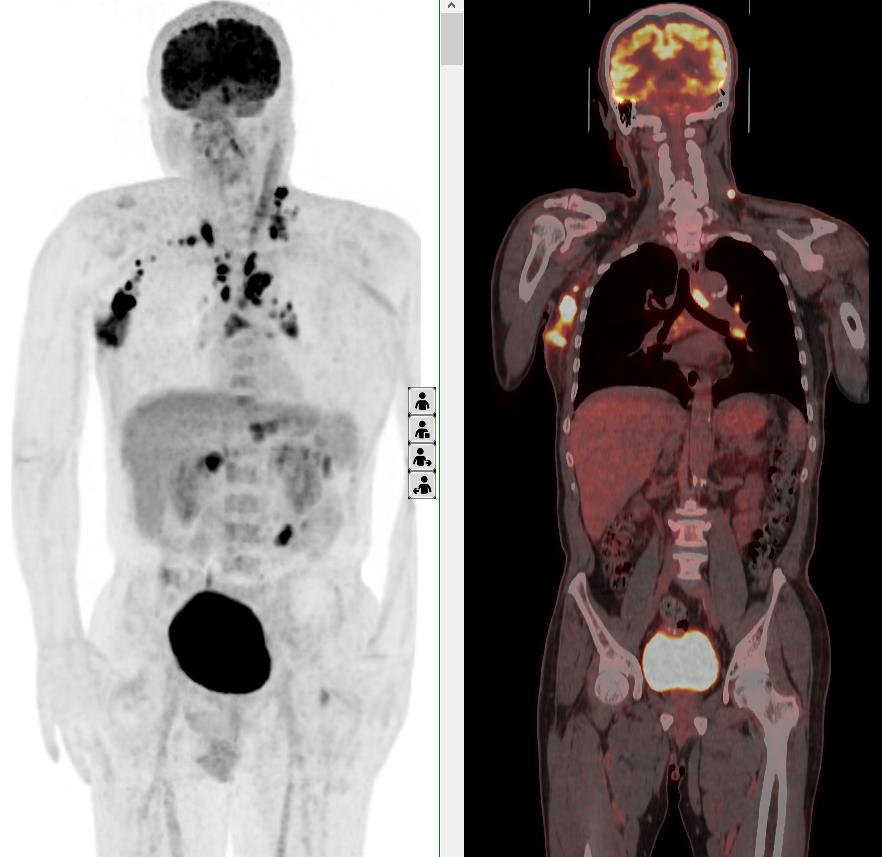

完善PET/CT檢查示:右側腋窩、雙側中下頸部、縱隔、雙側肺門多發MT,建議淋巴結活檢。后患者行右腋窩淋巴結切除活檢術,經北京大學第三醫院病理科會診示:右腋窩淋巴結惡性腫瘤,呈淋巴竇內生長模式,瘤細胞呈上皮樣,異型性明顯,伴中性粒細胞浸潤。結合病史及免疫組化,考慮為SMARCA4(BRG1)缺失的胸部腫瘤,伴神經內分泌標記表達。

本例為罕見病理類型的腫瘤,影像學表現無明顯特異性,診斷困難。強化CT和穿刺病理已基本明確為惡性腫瘤,行PET/CT檢查一是為了全身檢查,完善分期,二是根據PET代謝情況指導進行生物靶區活檢,進一步明確病理診斷。最終,PET/CT除縱隔病變外發現更多頸胸部淋巴結代謝異常,綜合考慮后對腋窩淋巴結進行切除活檢,最終得到病理證實。